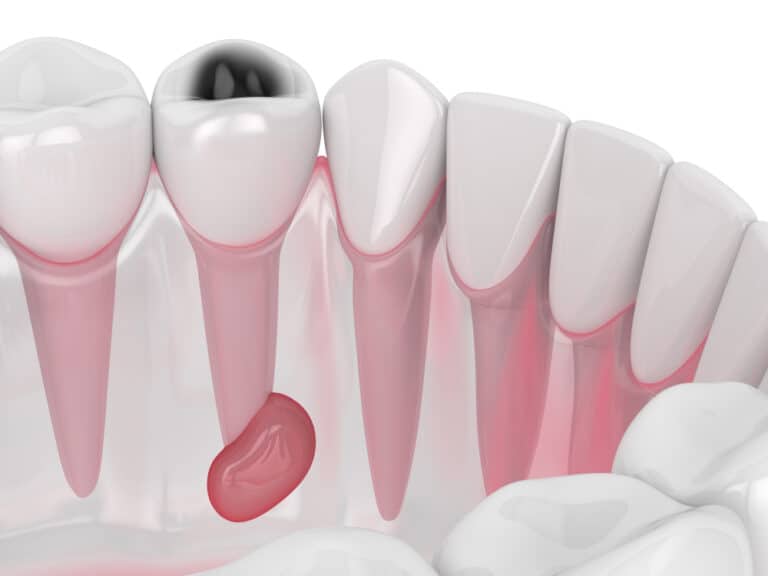

خراج الأسنان هو جيب من القيح يمكن أن يتشكل في أجزاء مختلفة من السن، نتيجةً لعدوىً بكتيرية، ويسبب ألماً متوسطاً أو شديداً لا يمكن تحمله، قد يمتد إلى الأذن أو الرقبة، ويمكن أن يتحول إلى حالة خطيرة تهدد الحياة إذا لم يُعالج.

حسب مكان حدوث الخراج، يمكن التمييز بين 3 أنواع أساسية للخراجات السنية؛ الأول هو الخراج القمي الذي يحدث عند طرف جذر السن، والثاني خراج دواعم السن الذي يحدث على اللثة بجانب جذر السن، وقد ينتشر إلى الأنسجة والعظام المحيطة، وأخيراً خراج اللثة الذي يحدث على اللثة.

السبب الرئيسي والوحيد لحدوث الخراج هو دخول البكتيريا إلى الأسنان أو اللثة؛ لكن يكمن الاختلاف في نوع الخراج، فخراج الأسنان القمي يحدث بسبب دخول البكتيريا إلى لب السن بسبب وجود نخر أو كسر في السن، أما خراج اللثة، فيحدث عند دخول جسم غريب في اللثة؛ مثل قشرة الفشار أو شعيرات فرشاة الأسنان؛ ما يؤدي إلى تراكم البكتيريا.

يجب أن يعالَج خراج السن في الحال؛ حتى لو تمزق وخرجت محتوياته، ومن الضروري زيارة طبيب الأسنان كي ينظف مكان الخراج جيداً من أية بقايا، ويصلح السن المصاب لمنع العدوى مرةً خرى، أما إذا تُرك الخراج دون علاج، فمن المحتمل أن تنتشر العدوى إلى الفك، وأجزاء أخرى من الرأس والرقبة، وحتى إلى الدماغ، وفي حالات نادرة؛ يمكن أن تنتقل البكتيريا إلى مجرى الدم وتسبب تلوث الدم؛ وهو عدوىً مهددة للحياة.